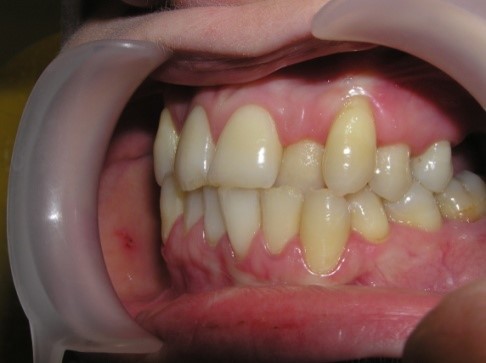

palatal location of the upper jaw incisors, flattening of the frontal area of

the upper jaw and lengthening of the frontal area of the lower jaw are

determined. In this case, exposure of the necks of the lower frontal teeth,

violation of their stability and inflammation of the gums may be observed, and

the clinic of catarrhal or atrophic gingivitis develops as a result of

functional trauma.